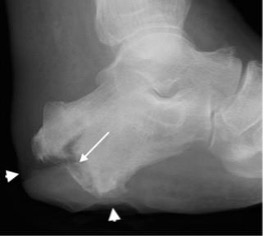

Abscess in distal tibia with sclerotic sequestrum on plain radiograph and CT (arrow)